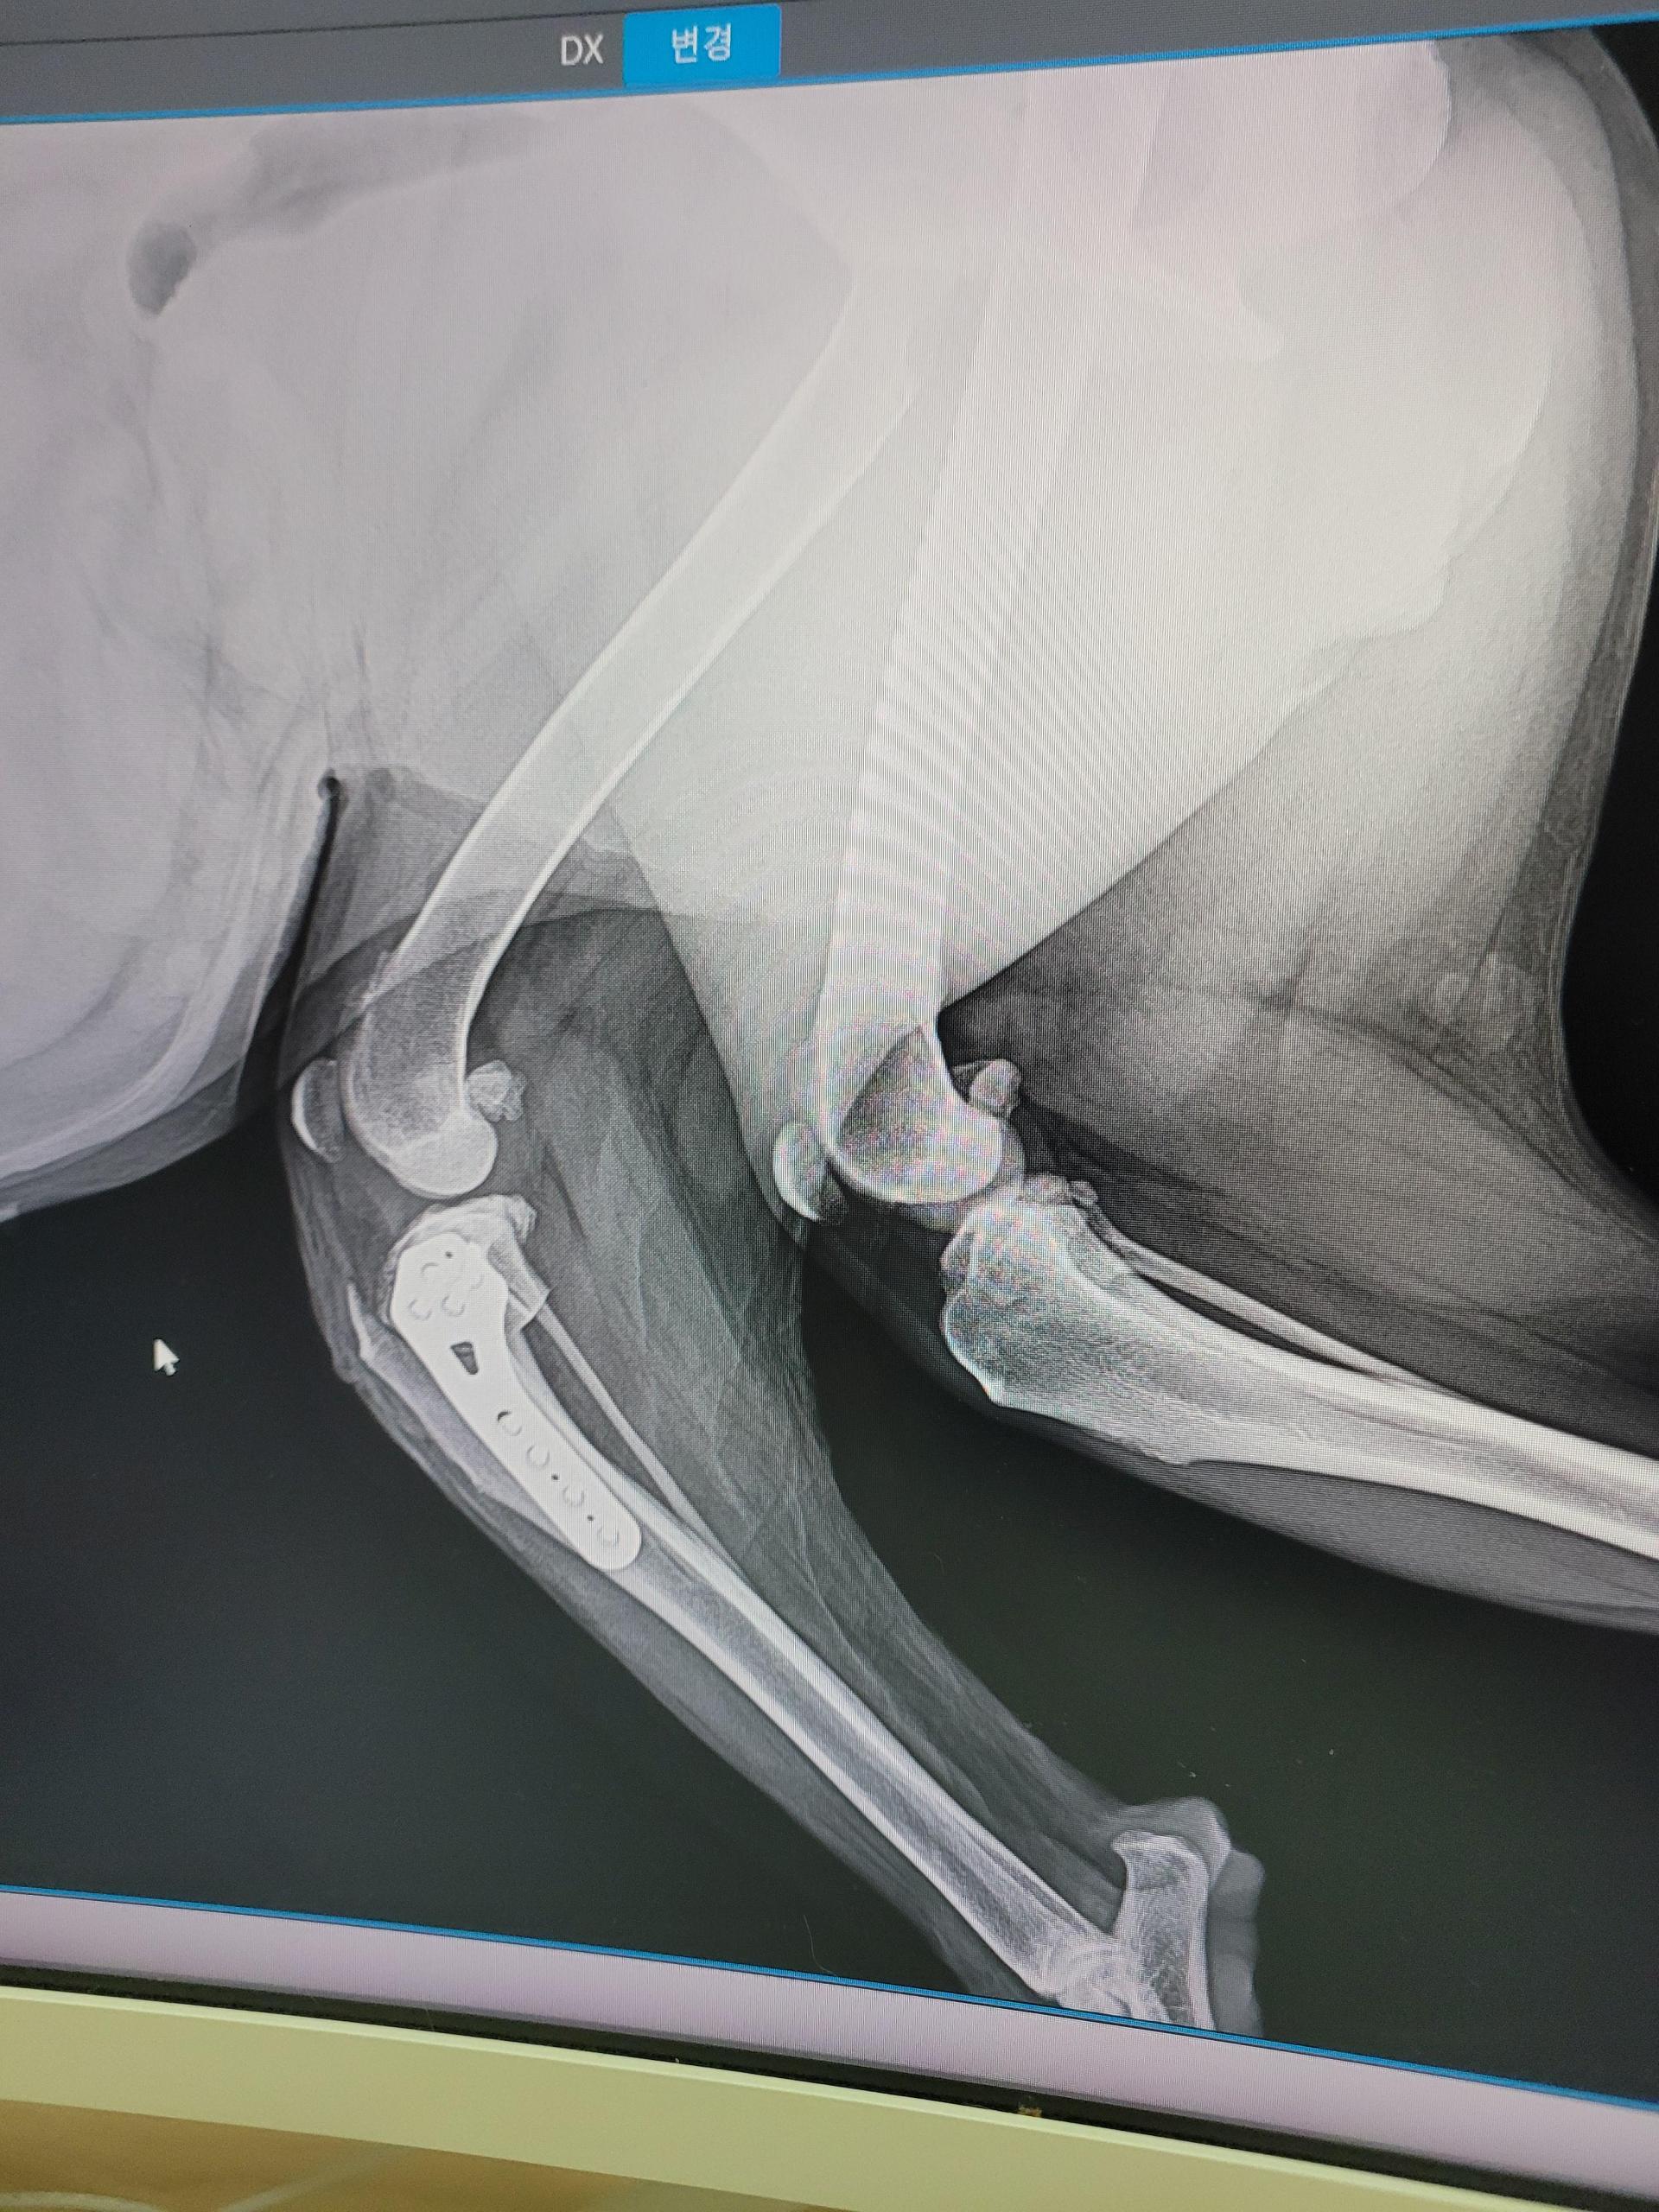

마침내, 9월 4일! 다시 한번 연맹의 도움으로 데이지는 TPLO 수술을 받았습니다.

좌측 전십자인대 단열로 인한 파행을 교정하기 위한 큰 도전이었죠.